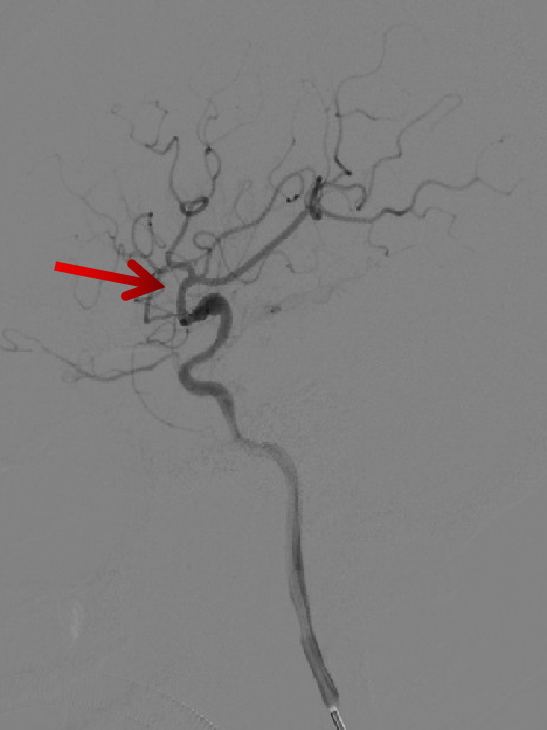

造影显示:左侧A1段血流纤细,左侧前循环供血通过右侧A1段及前交通代偿。

左侧颈内动脉末端梭形夹层动脉瘤,2.9mm*3.5mm。